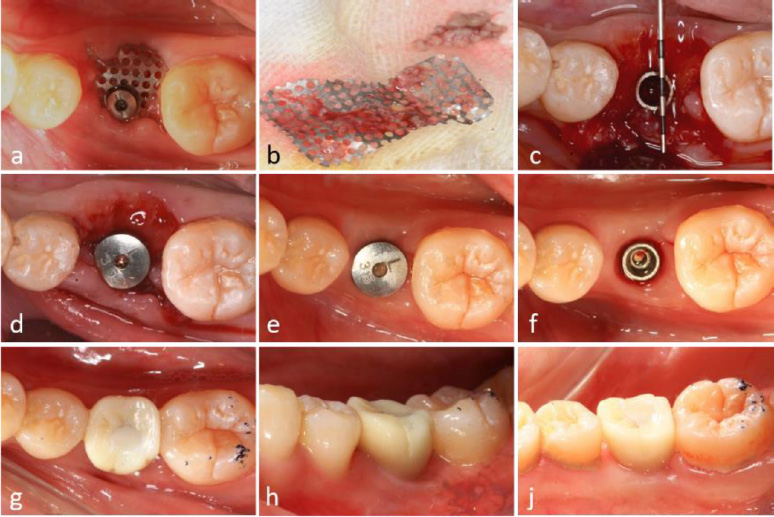

2.10. Removal of Titanium Mesh

Approximately two months postoperatively, soft tissue proliferation and epithelization were observed beneath the exposed titanium mesh. Despite the presence of debris and muck adhering to the mesh, no clinical signs of inflammation were detected (Fig. 4a).

During the re-entry procedure, the titanium mesh was found to be encased in dense connective tissue. The mesh was removed six months after the initial surgery, revealing that the space beneath it was occupied by tissue exhibiting macroscopic characteristics of newly formed bone (Fig. 4b, 4c).

Surgical procedures and clinical outcomes of second-stage implant surgery. (a) Intraoral view at 6-month postoperative follow-up, (b) Removal of titanium mesh demonstrating residual debris accumulation, (c) Significant alveolar ridge augmentation and soft tissue formation beneath the titanium mesh, (d) Placement of healing abutment for soft tissue conditioning, (e) Peri-implant soft tissue maturation at 4 months post-healing abutment placement, (f) Establishment of well-contoured peri-implant gingival architecture, (g-i) Intraoral clinical photographs illustrating final prosthetic rehabilitation outcomes.

2.11. Alveolar Ridge Augmentation

A significant increase in both the width and height of the alveolar ridge was achieved. A transmucosal healing abutment was placed for two weeks, followed by the completion of a single-tooth implant restoration, resulting in satisfactory aesthetic and functional outcomes (Fig. 4d-4i). Postoperatively, the vertical bone height on the buccal side increased by 5.1 mm and on the lingual side by 3.0 mm (Fig. 5a-5f). Slight reductions in these measurements were observed upon completion of the implant restoration, with the buccal and lingual vertical bone heights measuring 4.4 mm and 2.0 mm, respectively (Fig. 5b, 5e).

At the 2.5-year follow-up, the vertical bone height on the buccal side was maintained at 3.3 mm, while the lingual side measured 1.9 mm (Fig. 5c, 5f).

2.12. Clinical Outcomes

Partial exposure of the titanium mesh occurred during the application of the novel implant-supported tent technique. However, this did not adversely affect the bone regeneration process. Clinically and radiographically, a significant increase in alveolar ridge width and height was confirmed. The patient demonstrated both functional and aesthetic success throughout the 2.5-year follow-up period.